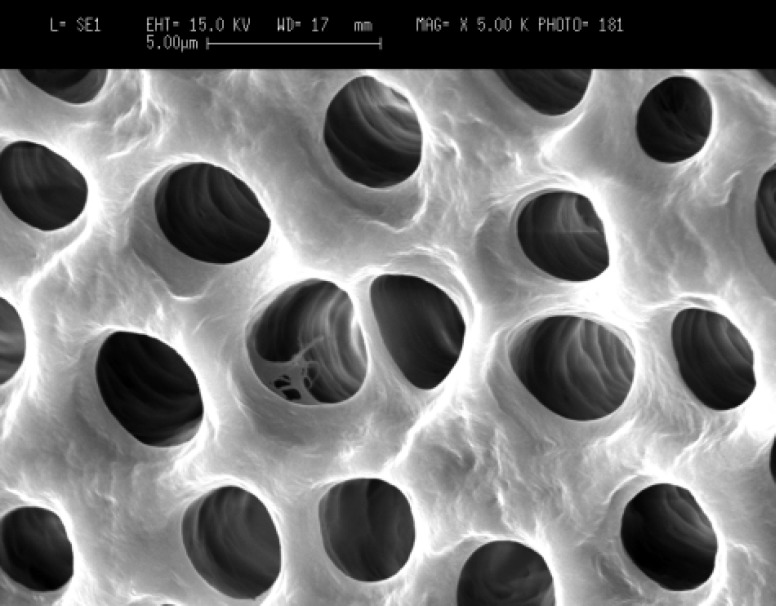

歯の内部の歯質は切削片などのが象牙細管に入りこみ、接着の技法、ダイレクトボンディングが阻害される可能性がありEr:Yagレーザーの水の爆発・ウオーターマイクロエクスプロージョン(20ナノメーターの水の爆発)により歯質である象牙細管がキレイに洗浄されます。

象牙質がキレイに洗浄されると接着が有効に働きます。そうでないとかなり危ないということになります。